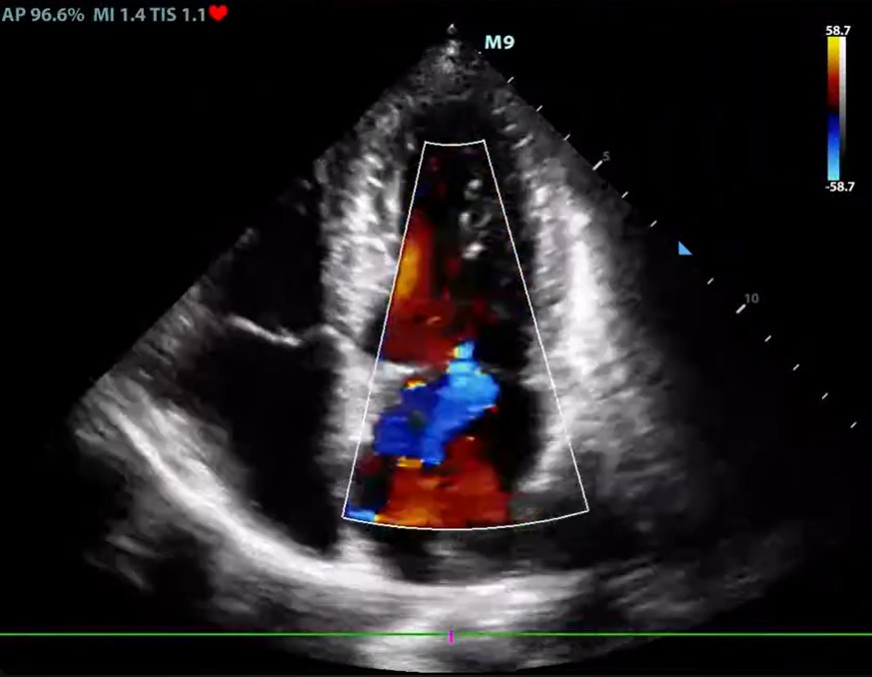

HDR Flow (High Dynamic Range Flow)